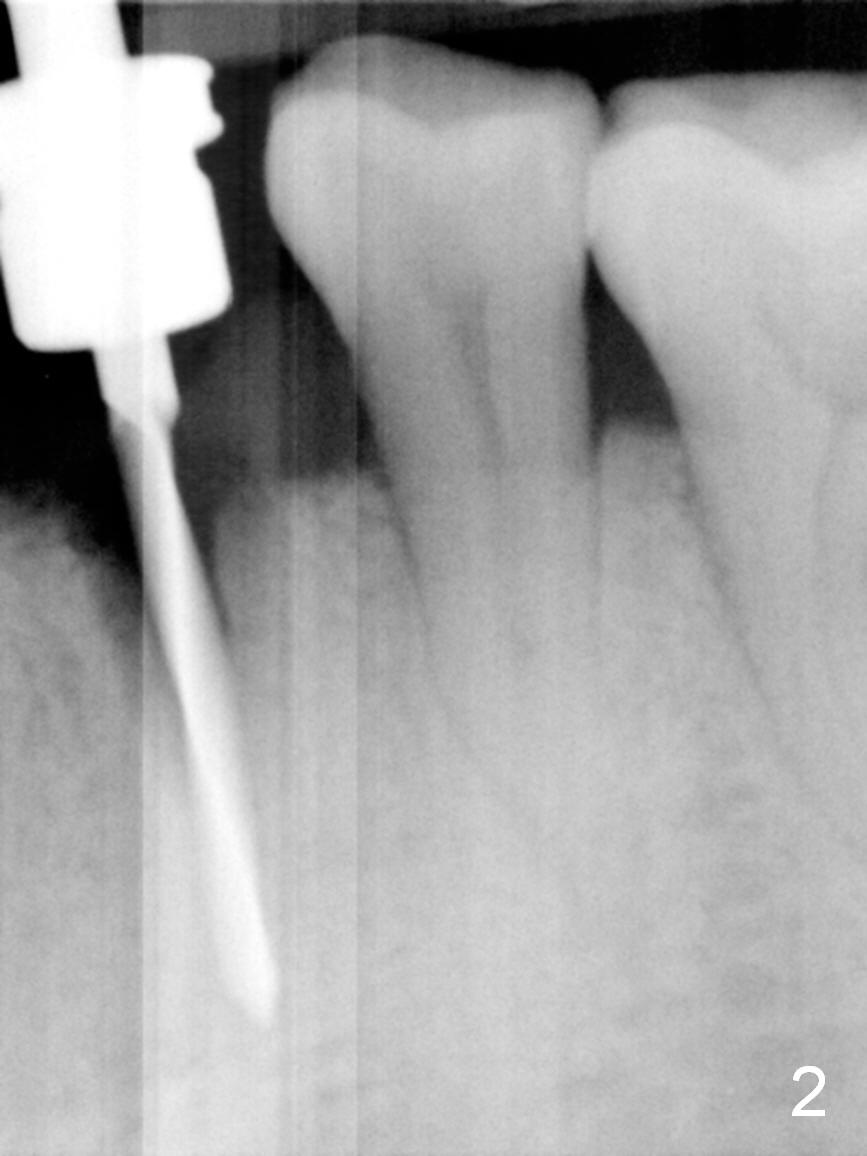

The residual root at #21 seems to be buccally positioned (Fig.1 *).  The initial osteotomy is established with the 1.6 mm drill at 11 mm (Fig.2).  Later the depth increases to 13 mm.  The initial osteotomy is found to be too lingual, but experience shows that as osteotomy increases in diameter, the trajectory would shift buccally due to the thick lingual plate (slope).  When 3.3 mm Magic drill reaches 11 mm, the patient feels pain.  It is probably due to the dense bone.  A 4x11 mm IBS implant cannot be seated due to high torque; it is removed.  The osteotomy is increased with 3.8 mm drill.  The implant is re-seated with >55 Ncm; it is over-lingually placed.  Due to failure to seat the implant driver completely, the implant cannot be un-torqued.  A 4.5 mm 15° angled abutment (3 mm cuff) is placed for immediate provisional (Fig.3,4 *).